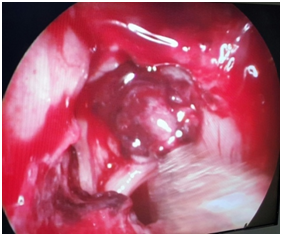

Before shifting patient to operation theatre, a repeat MR Angiography was done to ensure that there is a stable thrombus at the injury site before pack removal. It showed an ill defined hypodense areas involving gray and white matter in left frontal and parietal lobes in the region of ACA-MCA and MCA-PCA watershed territories respectively, suggestive of watershed territory infracts. Ill defined hypodense areas suggestive of infracts are seen in left centrum semiovale in vicinity of central sulcus (Figure 2) and loss of signal intensity in petrous, cavernous and supraclival part of left ICA (Figure 3). Nasal pack removed under GA with no re-bleeding from injured site. Clot was seen over the injured part of ICA in the left sphenoid sinus plugging the LT ICA (Figure 4). Postoperative antiplatelet therapy continued augmented with physiotherapy.

Figure 4 ICA Clot after immediate removal of nasal packing.

Patient was mobilized by 3rd postop day with support and intensive physiotherapy was started. By 5th day he started walking and by the end of a week his Power in limbs of right side improved. Post op regular every day endoscopic suction toileting of nasal cavity and PNS was done carefully so as to avoid any infection or crusts and to assess how clot is organizing over the injured part of Lt ICA in left sphenoid sinus (Figure 5). At 3weeks the clot was fully flushed with bony canal of ICA and almost became indistinguishable. MRI showed improvement in the circulation at the infarct areas. The patient regained all his motor functions by 4weeks and he could do all normal activities.